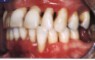

"PARODONTOSE"

ist der landläufige Begriff für Zahnfleischentzündungen. Der Patient bemerkt meistens, daß das Zahnfleisch blutet oder daß die Zähne länger als früher aussehen.

Entzündungen durch Beläge